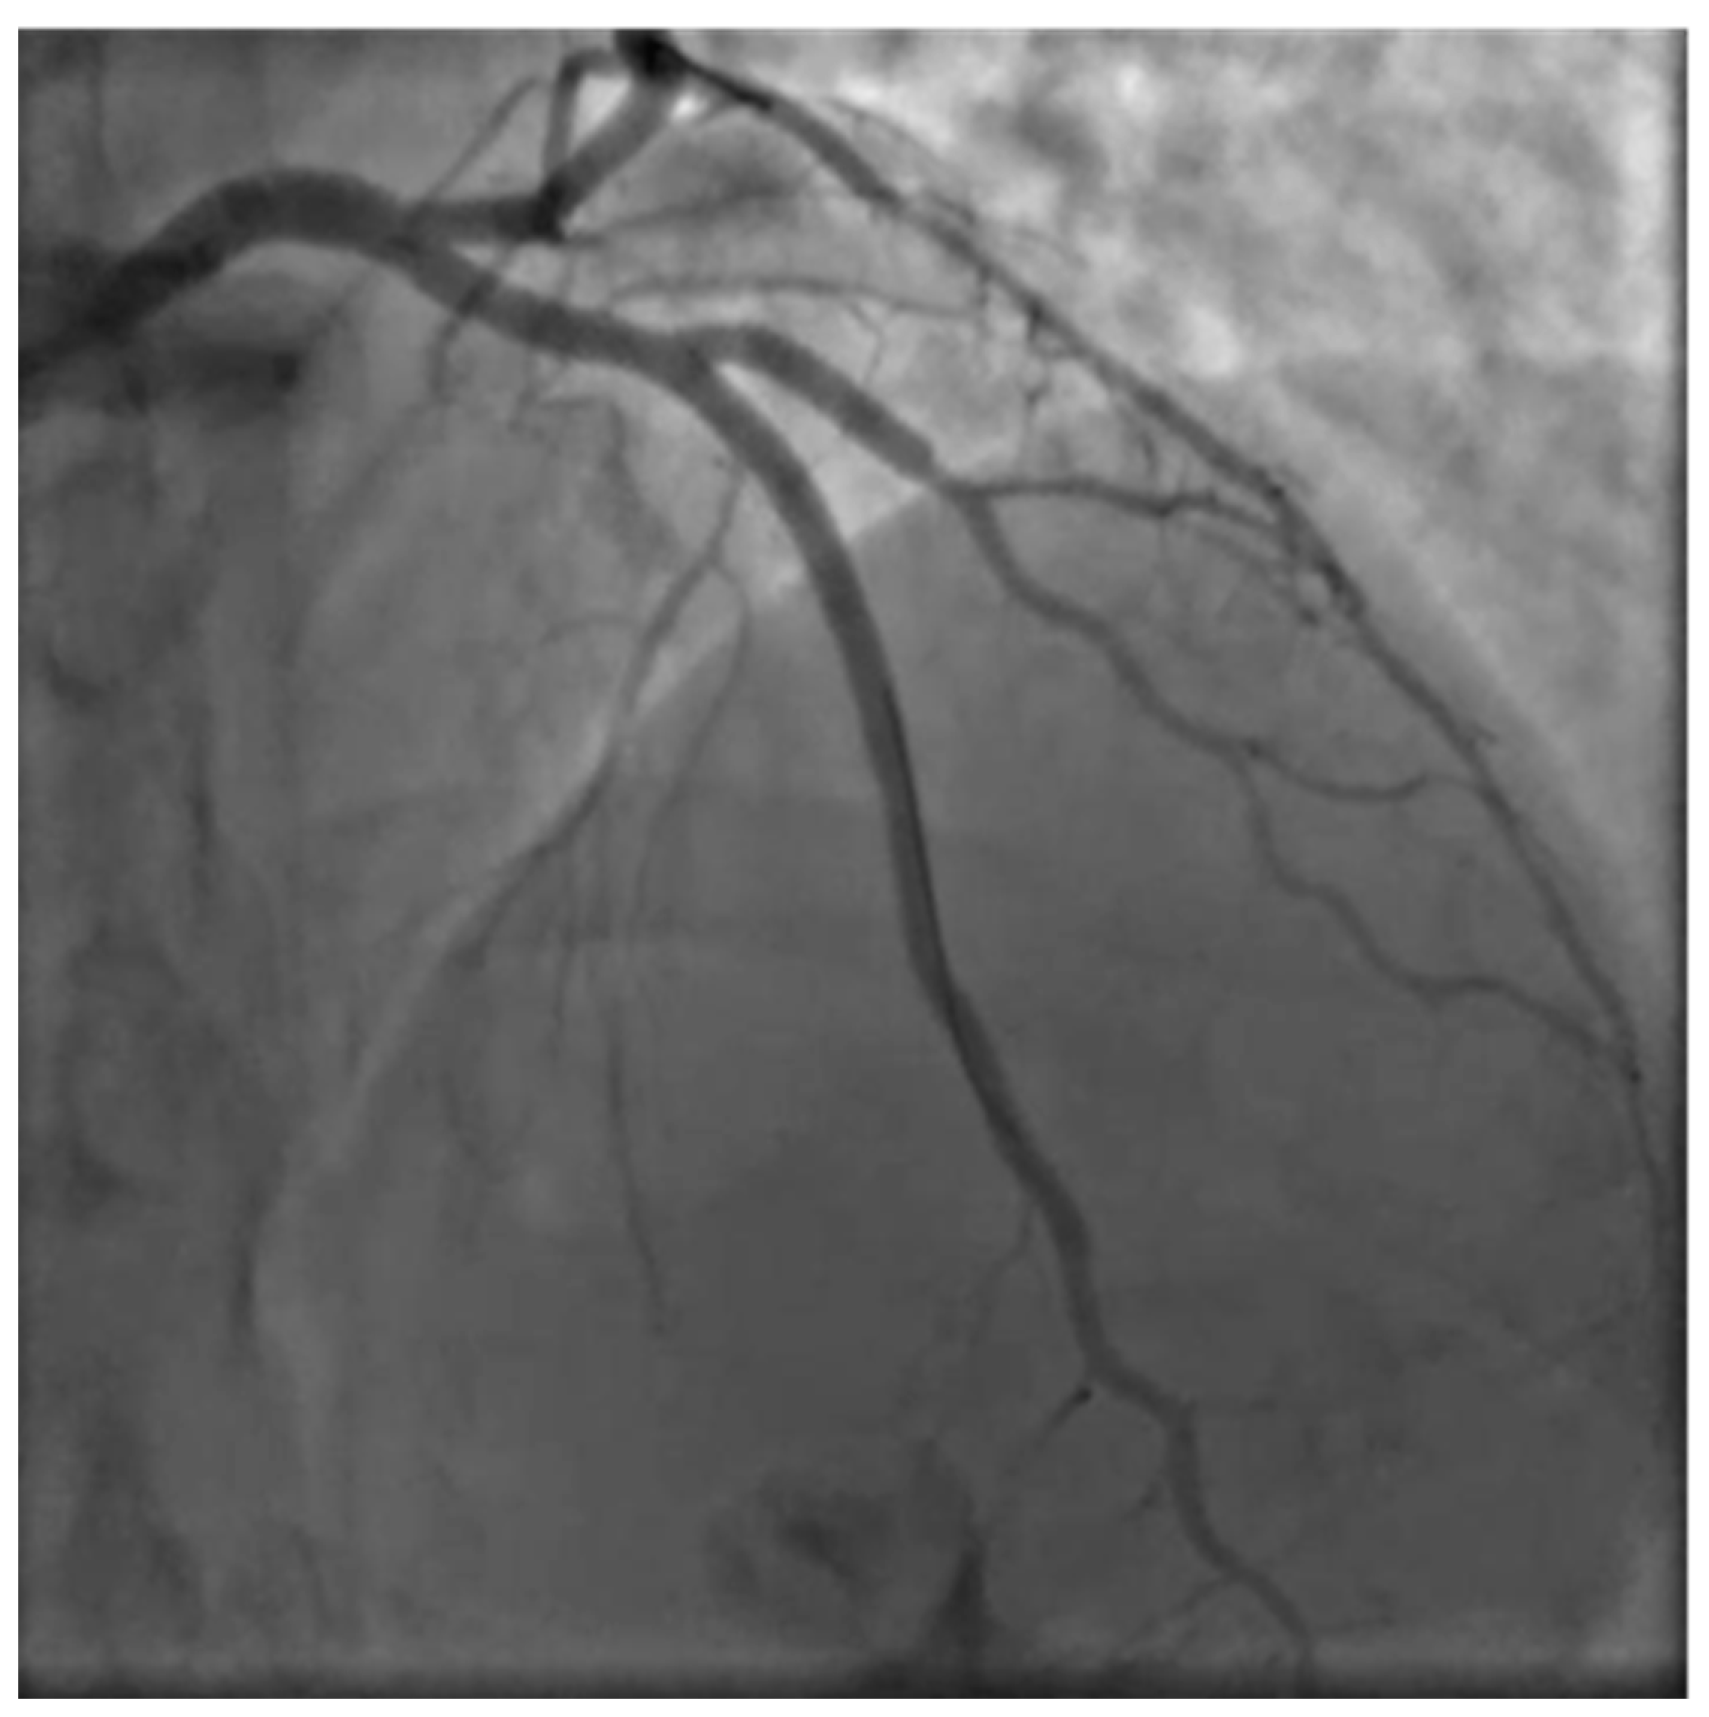

M.G. is a 38 years old woman with two previous pregnancies (G2P2), who was 36 weeks of gestation in her third uneventful pregnancy. All the ultrasound scans (US) performed highlighted a regular fetal growth and normal placental functional markers (umbilical Doppler Pulsatility index), Figure 1 and Figure 2. Her only known risk factor is smoking, which she had temporarily quitted.

Figure 1. Sonogram depicting a normal placenta US imaging.